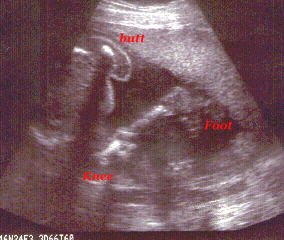

Can you see my foot?